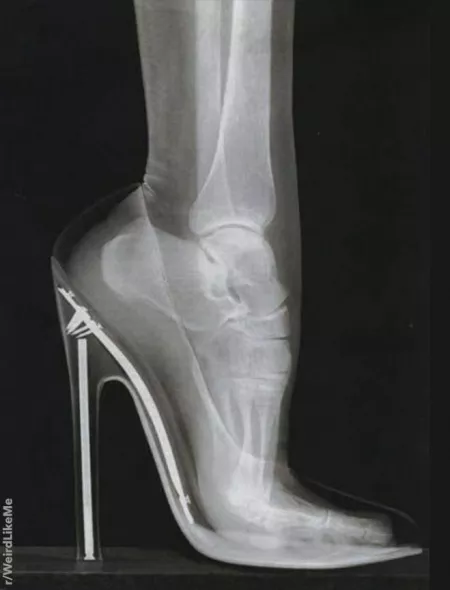

Category: heels